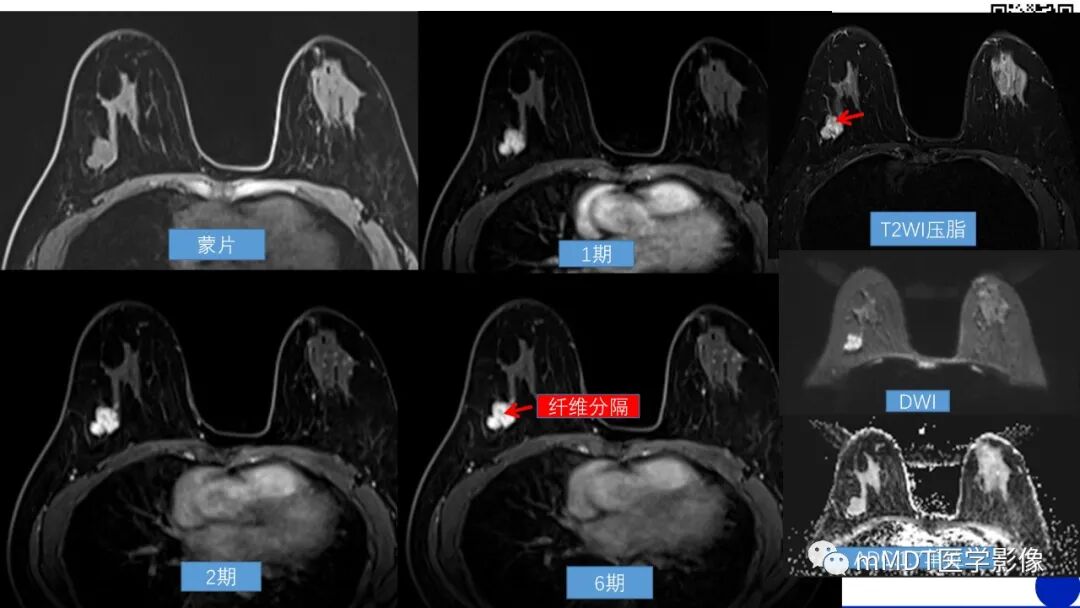

其二,这个病灶分叶较明显,其内有无强化的分隔,病理上叶状肿瘤和纤维腺瘤都属于一类,纤维上皮性肿瘤,既有上皮组织又有间质成分,只是叶状肿瘤有个分叶状的外观,间质细胞比较丰富,大家看病理图

其三,磁共振,形态学,不规则形或椭圆形肿块,边缘清晰,血流动力学:增强早期快速强化,延迟期渐增型,功能成像:ADC不低,三方面都支持良性,所以这个病灶可以归到3类,如果不放心4A类也没问题,如果结合临床查体可能更准确

给大家补充一例叶状肿瘤2级的

这例典型[强]

半年前曾经做过一次手术是叶状肿瘤2级,现在复发了,39岁好像,年龄略偏轻了一些

李老师的这个病例特别好,为大家开阔了思路,分叶状肿块生长较快的要考虑叶状肿瘤的可能,在病理类型上大家定到纤维上皮性肿瘤即可,尤其是磁共振上无强化的分隔在诊断时也是比较重要的参考依据